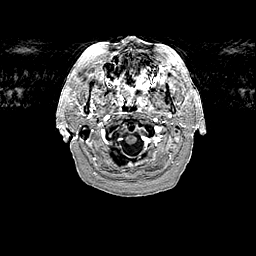

Glioma overlay -- Slice #5

[Home][Help][Clinical] Slice 5